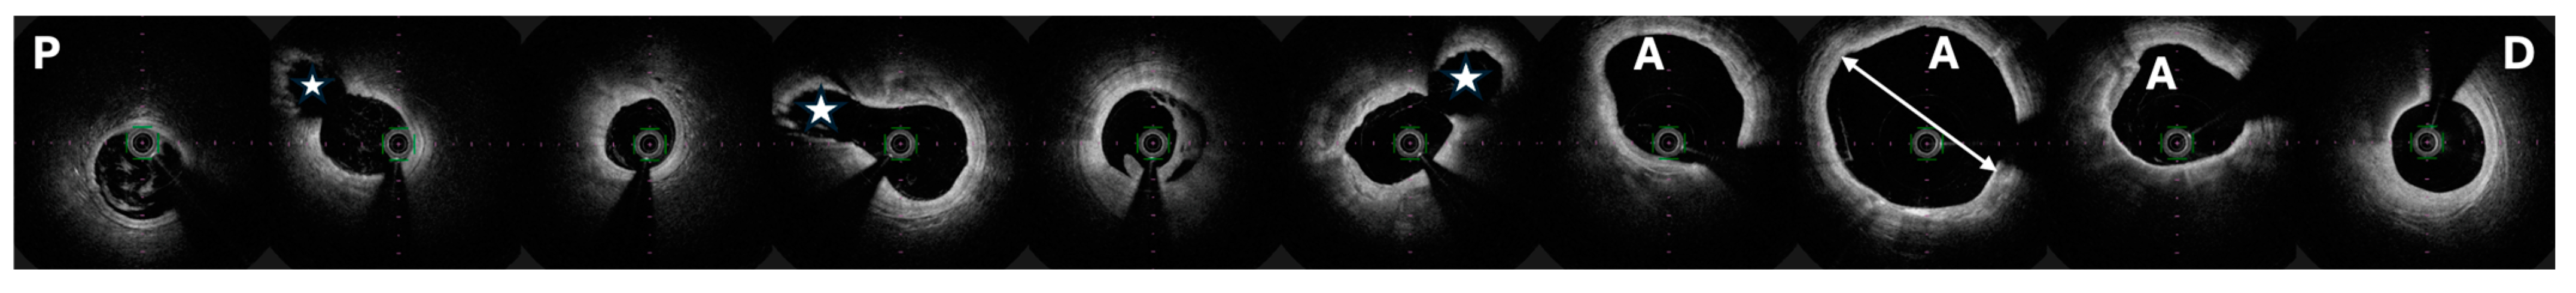

4. Diagnostics